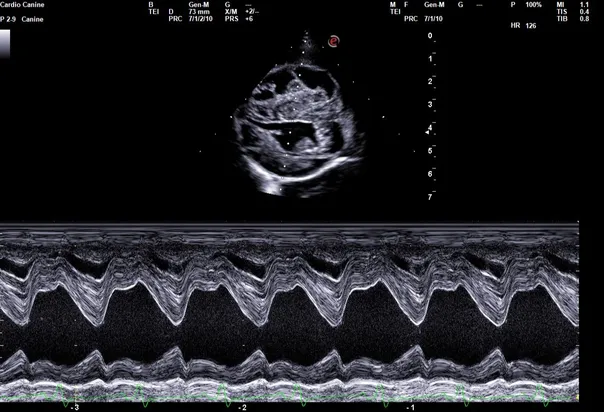

Echo image

Echocardiogram (cardiac ultrasound)

The Animal Medical Center offers in house echocardiograms. Our advanced ultrasound machine and specialized training allows us to provide a comprehensive ultrasound screening of the heart. Dr. Adam Deeke performs the echocardiogram and the images are then sent to a veterinary cardiologist for review. The cardiologist generates a reports which includes all findings, treatment and follow up recommendations. Echocardiograms are recommended for any dog or cat with a heart murmur, heart enlargement, arrhythmia, fainting, or exercise fatigue.